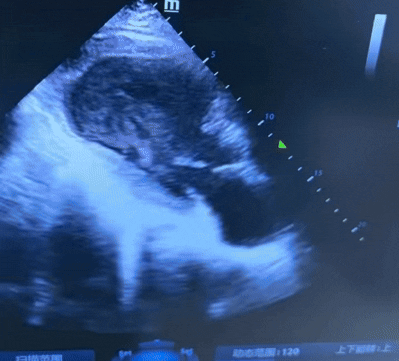

入院前7天:无明显诱因出现乏力、大汗症状;外院心脏彩超显示左心室室壁瘤(大小约58mm×55mm),左室射血分数(EF)24%。

EF 19%,左心室心尖部室壁瘤形成,心尖部稍高及低回声,考虑血栓形成。